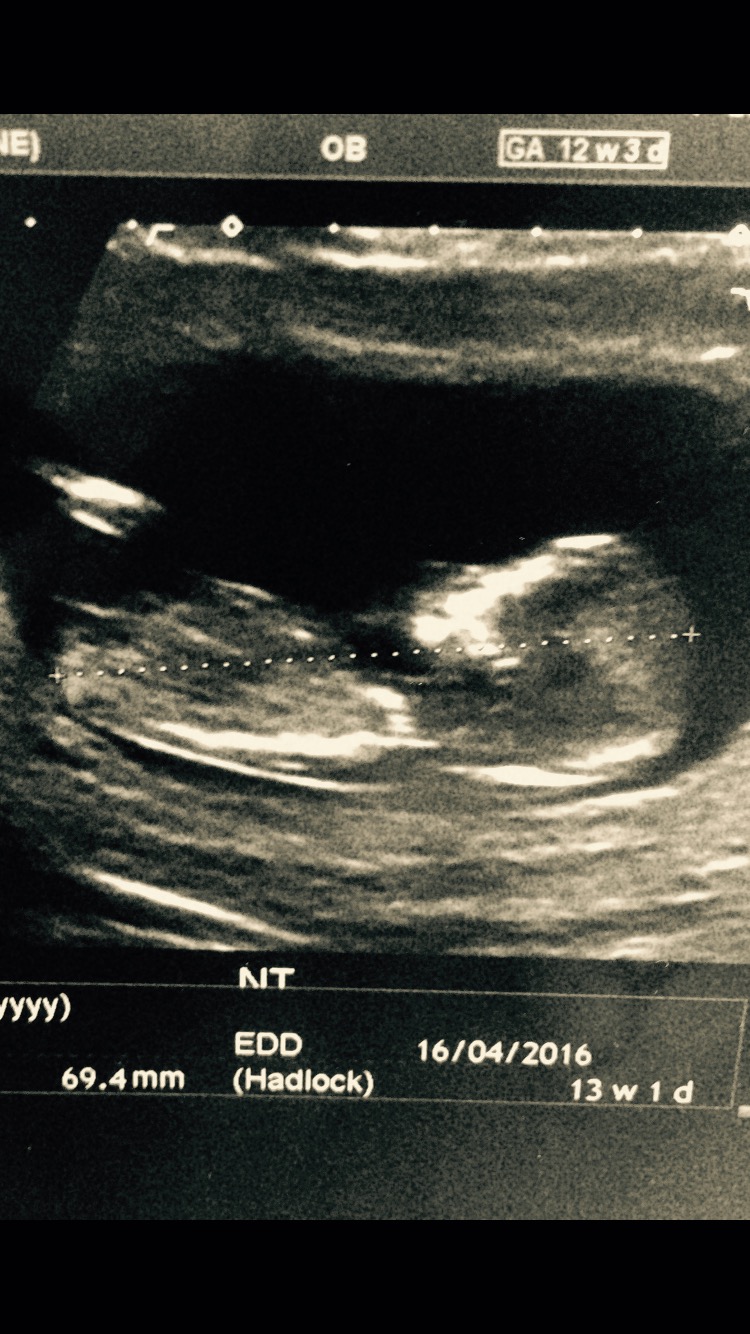

Do you have a nub shot from 12-13wk mark? Also did tech give any indication of gender at 20wk scan?

I have these 2 from 13w 2d